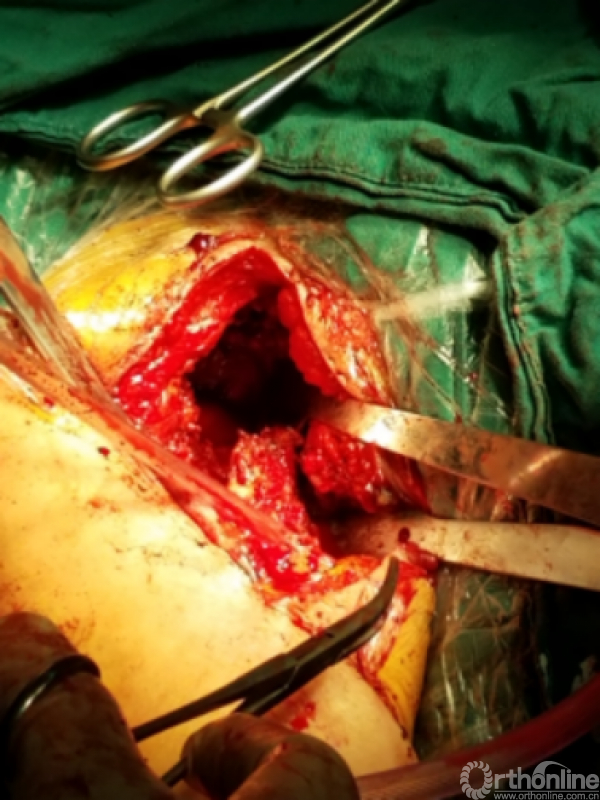

窦道周围见明显分泌物约10毫升

困难重重:

1、广泛粘连,解剖层次不清

2、广泛点状出血灶

3、分不清间隙

4、盂肱关节正常结构位置改变,关节囊瘢痕挛缩替代

5、屈曲外旋看不见关节间隙活动

手术过程:

1.从近端关节前外侧逐步下行,切除瘢痕

2.用食指逐步探查

3.以骨面硬质感为基准从中央部位向两侧分离

4.骨撬,骨膜剥离器协助分离内外侧间隙

5.以缺损处为中心向四周扩大显露

咬出增生骨痂及清理瘢痕组织后显露出原肩袖缝线,杂乱,完整,表面见有脓性组织

瘢痕发硬,变性,周围包裹纤维软骨痂

由于解剖结构紊乱,头静脉已消失。旋肱后动脉,弓状动脉剥离时出血,位于外侧转弯处,行填塞止血。

显露出肱骨头假体柄处

开始向内上扩大显露

注意事项:  肱骨头内移至喙突处,位于后内侧下方已有骨桥连接

特别小心腋鞘及臂丛神经

提示无法顺利脱位!!!

小心咬出间隙后,牵引肘关节前屈肩关节后伸外旋,拉钩撬拨脱位!!

关节盂正常结构消失,至喙突偏内侧部位,上方紧贴肩峰下,仍然有骨质可用!

咬除连接骨桥,清理髓腔,恢复活动度